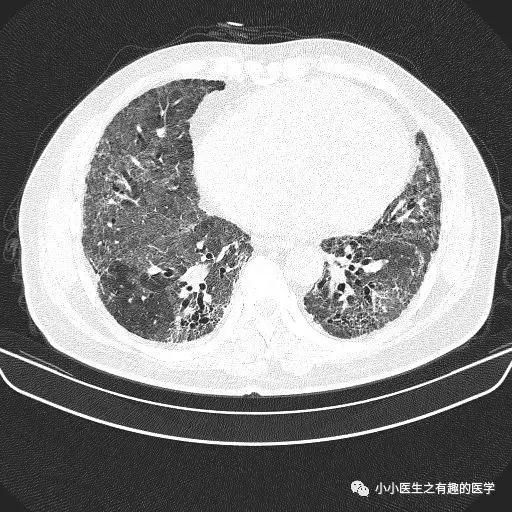

经典的间质性肺炎,就是一张网!

1.胸膜下2.网格状很多间质性肺炎,都有这个特征,是间质性肺炎的入门知识,也是很重要的知识。

乌漆嘛黑的是肺气肿。

间质性肺炎 合并 肺气肿